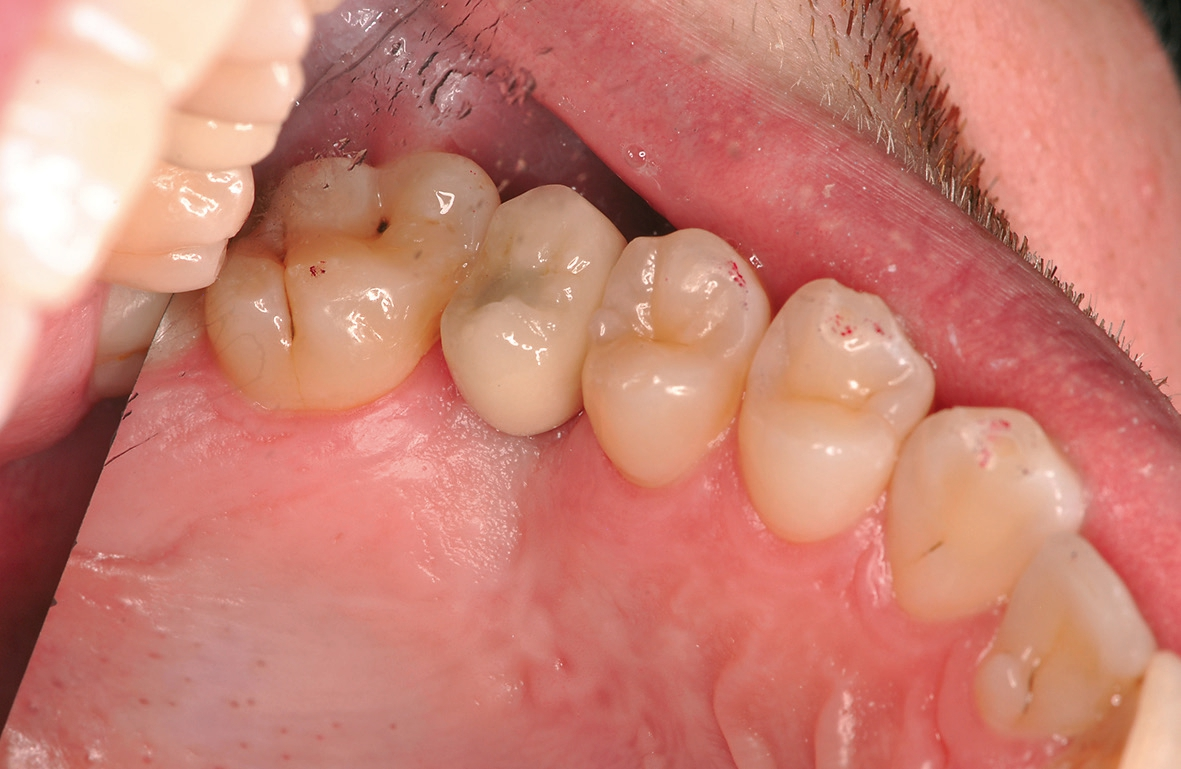

Nach einer sechsmonatigen Einheilzeit wurde das Implantat freigelegt und die Fixierungskappe entfernt. Es folgte die handfeste Insertion des Healingabutments. Das Healingabutment wurde für drei Wochen getragen, um das Emergenzprofil zu formen. Nach Ausformung des Emergenzprofils wurde das Healingabutment temporär für die Implantatabformung entfernt und der Abformpfosten eingeschraubt und radiologisch auf Passgenauigkeit kontrolliert (Abb. 22). Die offene Abformung erfolgte mittels individuellem Abformlöffel und Vinyl-Polyether-Silikon. Es wurde eine verschraubbare Krone aus Lithium-Disilikat-Glaskeramik (IPS e-max CAD, Ivoclar Vivadent, FL-Schaan) angefertigt und mit 20 Ncm festgeschraubt. Die Schraube im Schraubenkanal wurde mit einem Schaumstoffpellet isoliert und der Kanal mit niedrig viskösem Kunststoff versiegelt (Abb. 23).

Eine Verlaufskontrolle acht Monate nach Versorgung des Implantats zeigte keine Veränderungen und somit stabile Verhältnisse (Abb. 24).